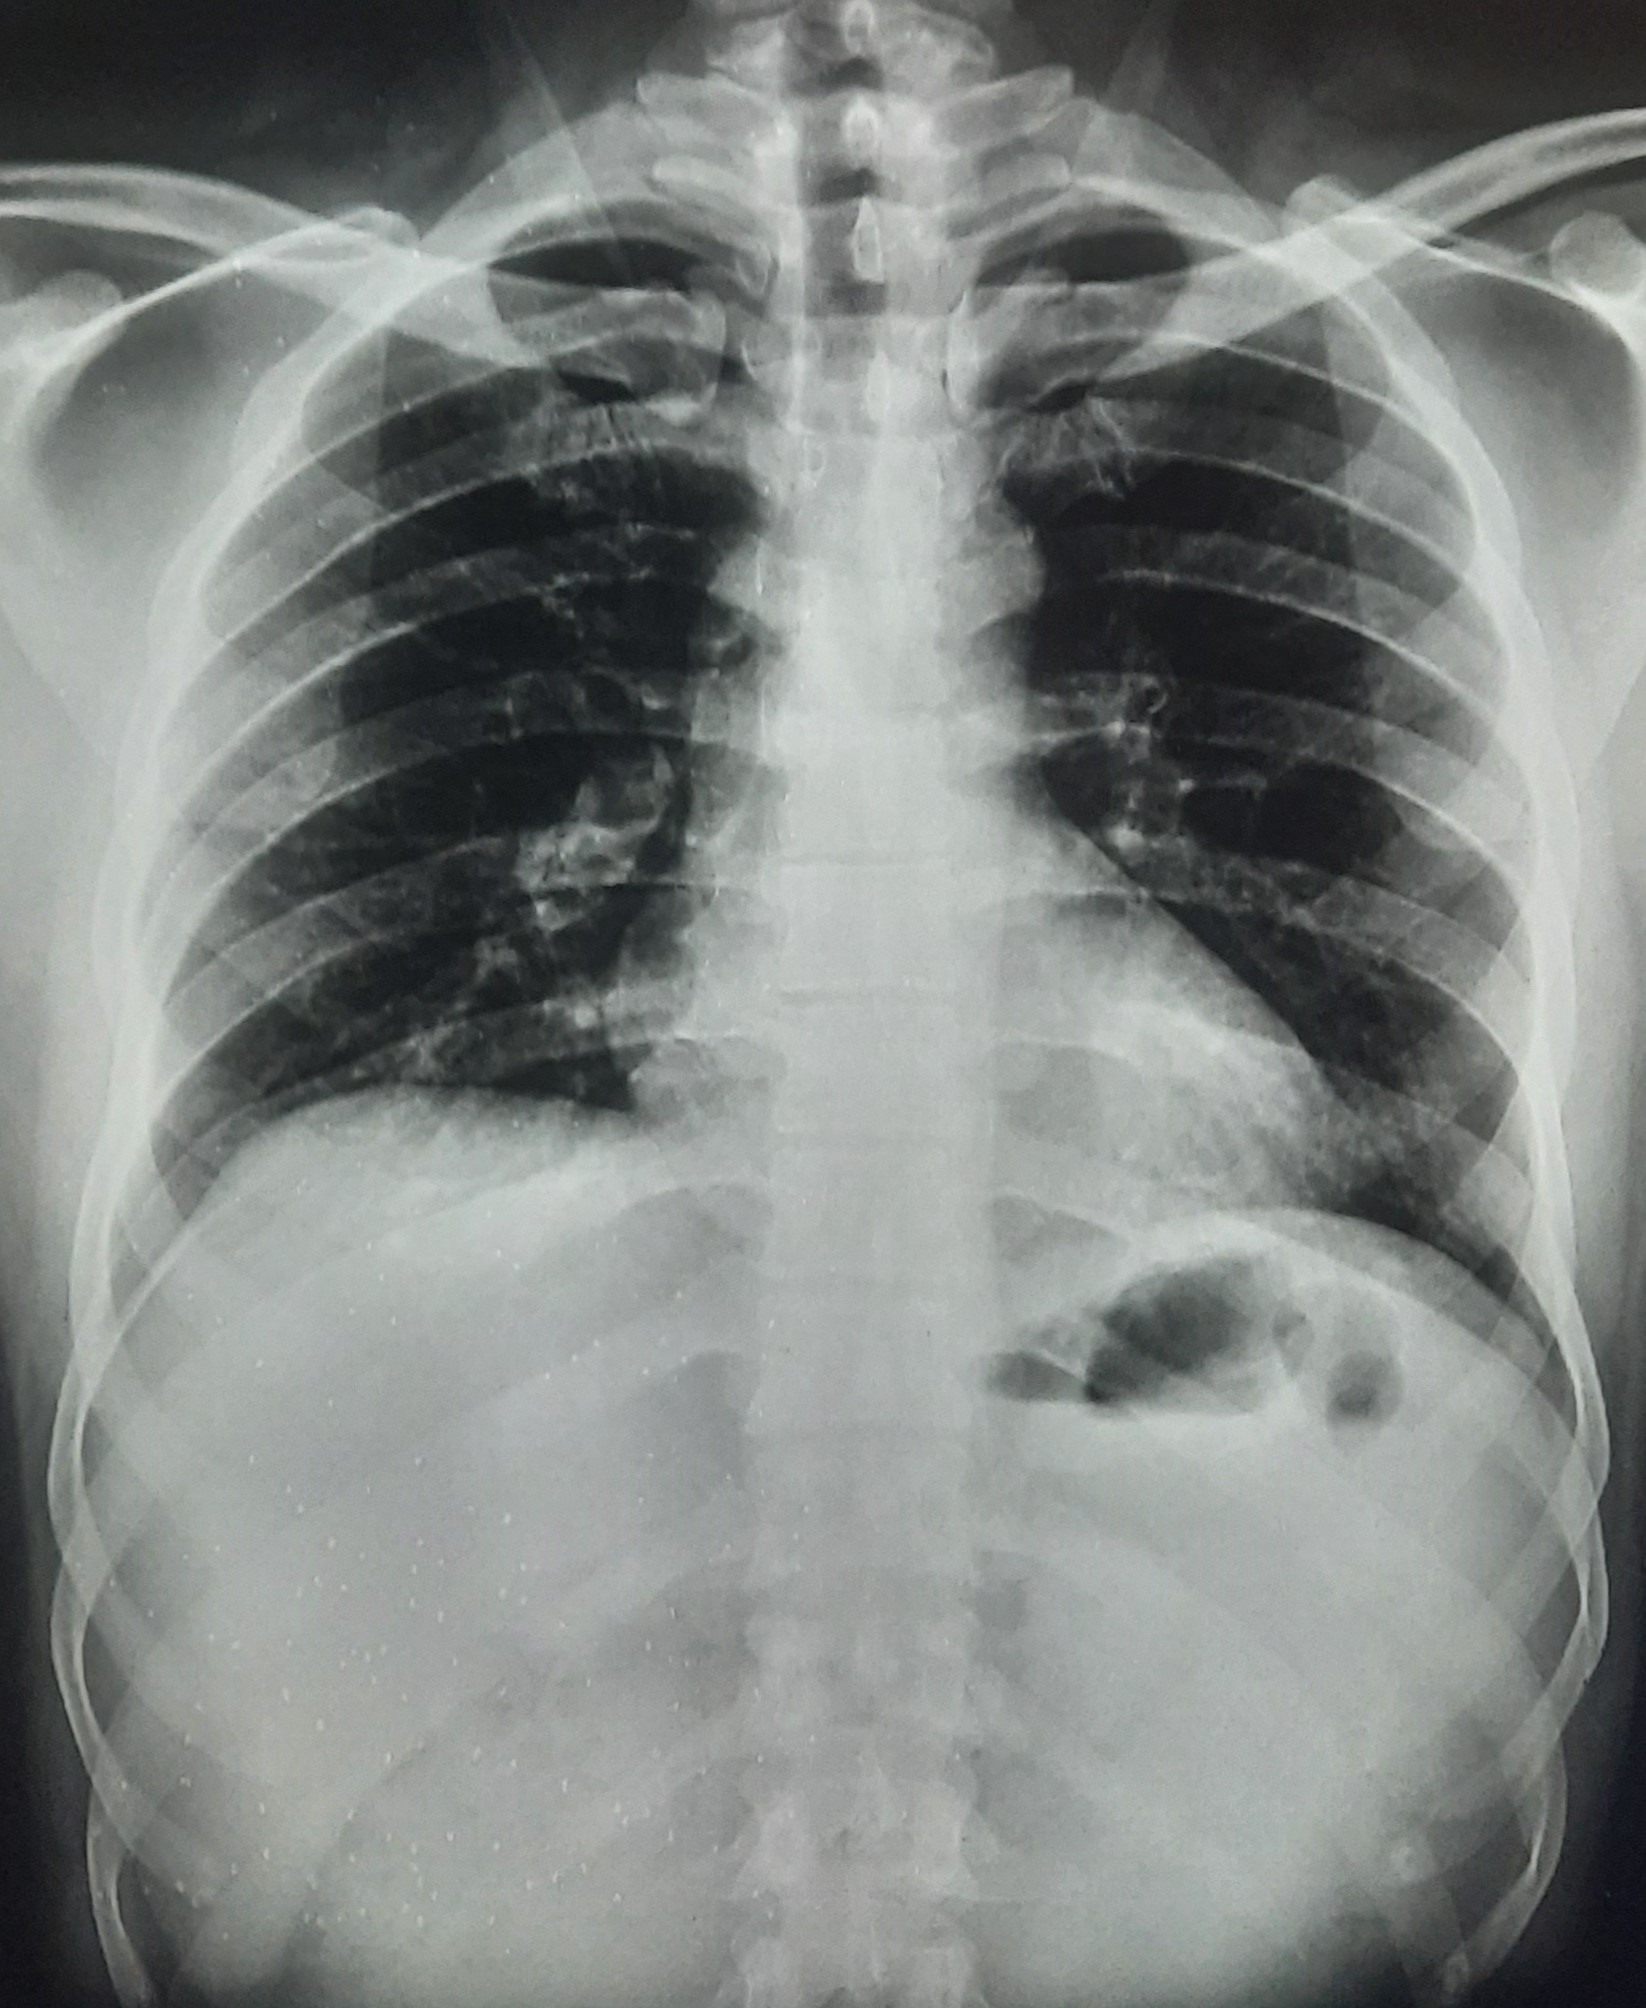

| 251 | IGGMC, Nagpur, Nagpur | P2 | 29-4221 | Ganpat Gaikawad | Consent taken on Paper | 70 Yrs. |

Provisional Diag : post TB sequele?

Final Diag : Fibrosis |

Non-TB Case (Confirmed) | Fibrosis | Abnormality visible on x-ray |